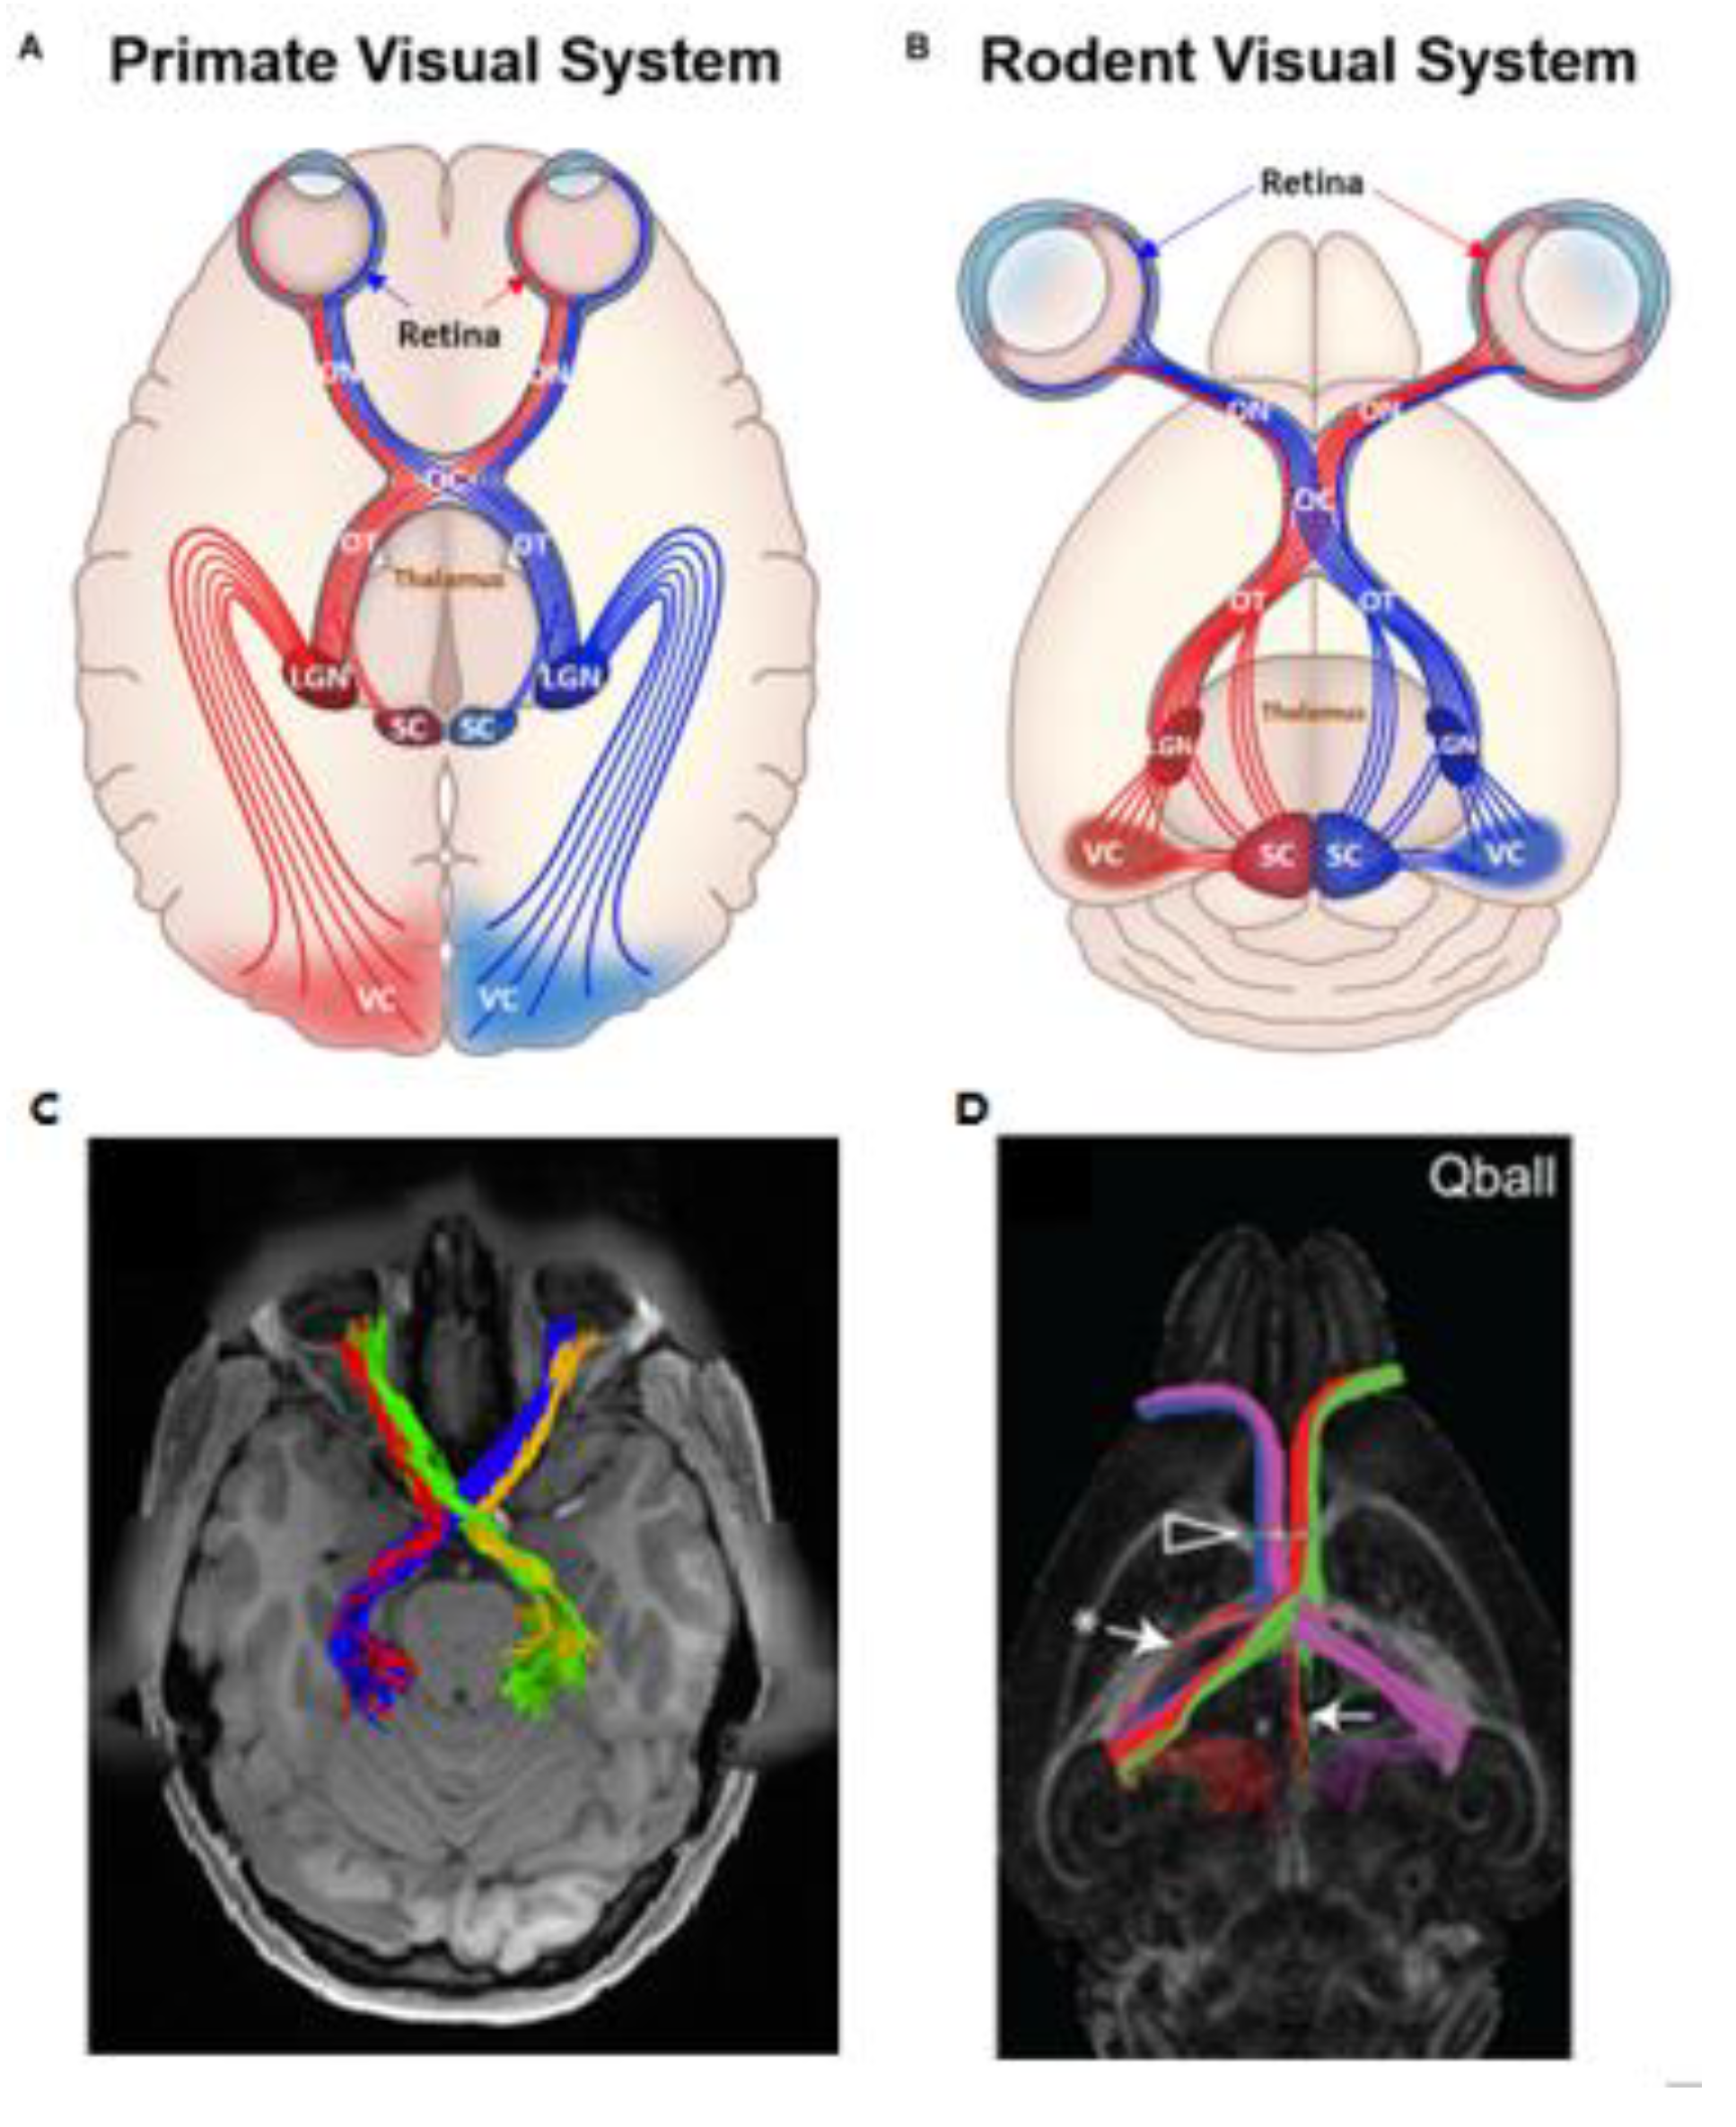

- He, J.; Zhang, F.; Xie, G.; Yao, S.; Feng, Y.; Bastos, D.C.A.; Rathi, Y.; Makris, N.; Kikinis, R.; Golby, A.J.; et al. Comparison of multiple tractography methods for reconstruction of the retinogeniculate visual pathway using diffusion MRI. Hum. Brain Mapp. 2021, 42, 3887–3904. [Google Scholar] [CrossRef]

- Moldrich, R.X.; Pannek, K.; Hoch, R.; Rubenstein, J.L.; Kurniawan, N.D.; Richards, L.J. Comparative mouse brain tractography of diffusion magnetic resonance imaging. NeuroImage 2010, 51, 1027–1036. [Google Scholar] [CrossRef]

- Yamada, M.; Momoshima, S.; Masutani, Y.; Fujiyoshi, K.; Abe, O.; Nakamura, M.; Aoki, S.; Tamaoki, N.; Okano, H. Diffusion-tensor neuronal fiber tractography and manganese-enhanced mr imaging of primate visual pathway in the common marmoset: Preliminary results. Radiology 2008, 249, 855–864. [Google Scholar] [CrossRef]